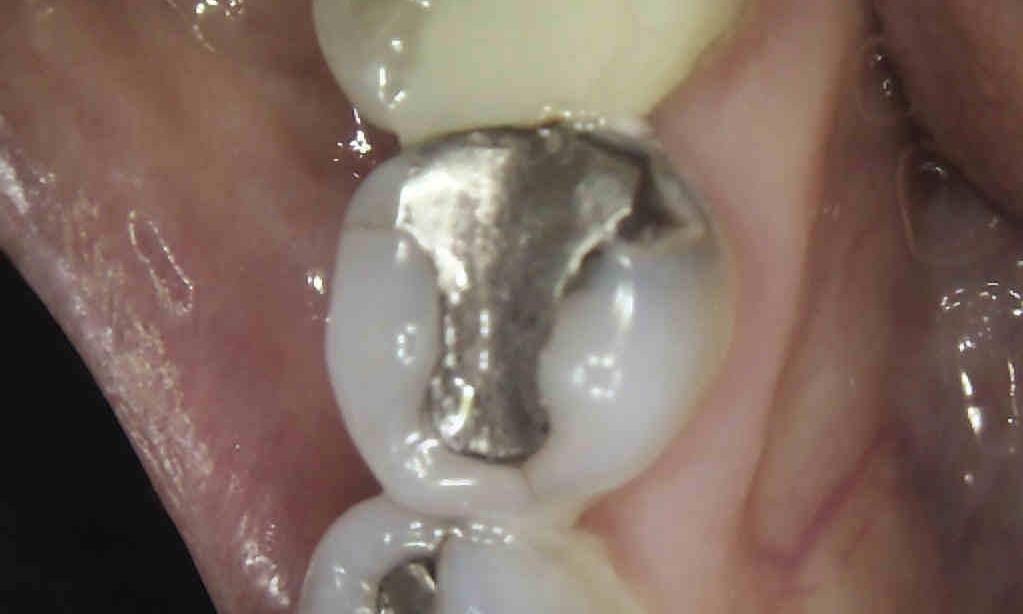

This patient presented to our office with a failing amalgam (silver) filling. After removing the old restoration, we treated the cavity from underneath it. We then placed a more esthetic composite restoration. The patient was thrilled.